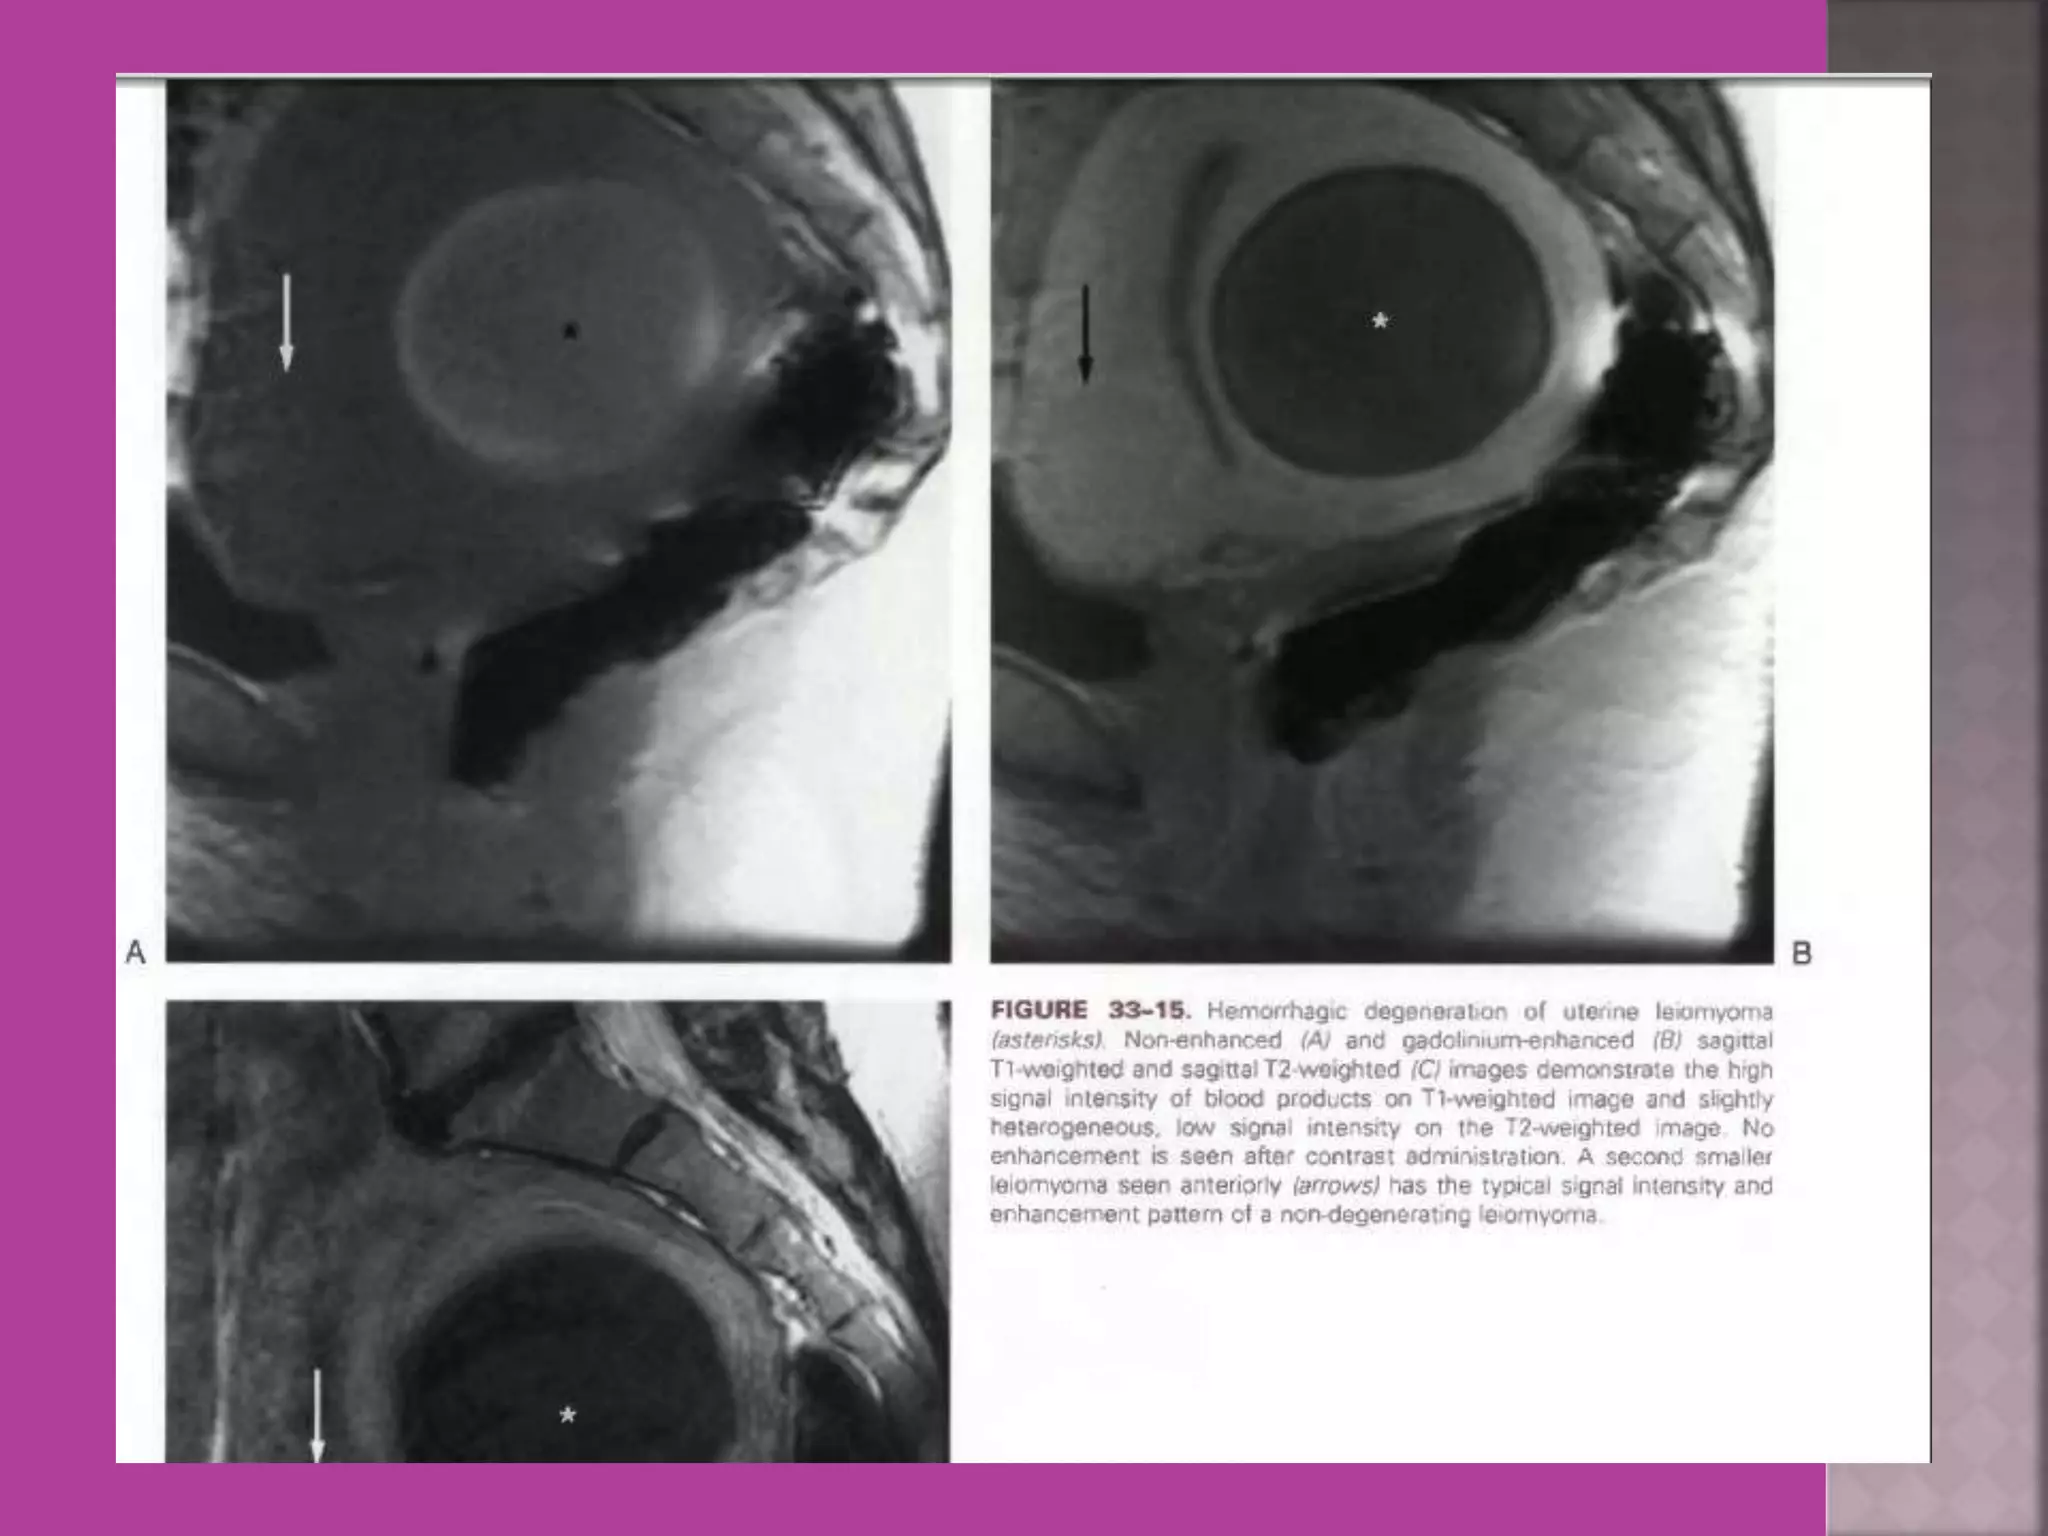

Degeneration Of Fibroid

Cystic Degeneration of

Fibroid